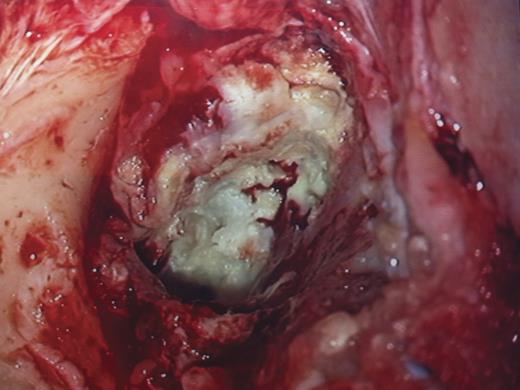

At surgery, transmeatal exicision of the EAC osteoma revealed an underlying cholesteatoma that has caused bony erosion of the inferior canal wall (Fig. 2) and formed a fistulous connection to the overlying neck skin (Fig. 3). The post-aural sinus and fistula were excised through a post-auricular incision. A cortical mastoidectomy was performed to explore the mastoid cavity, which was found to be disease free. The temporalis fascia was harvested and used to reconstruct the inferior canal wall defect. Histopathologic examination of the excised tissues confirmed the synchronous dual pathology involving the EAC (Figs 4 and 5).